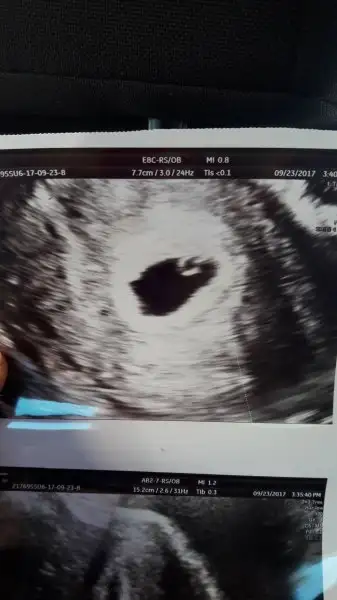

Valla herkes söylemiş aslında. Dedikleri de çok doğru. Boş gebelikte yolk sac olmuyor Can'ım. Rahat ol artık. Görürsün bebişi kalp atışı ile beraber.Kızlar benimki boş gebelik olabilir mi doktor yolk sac izlendi embriyo izlenmedi yazdı ultrason kağıdına betam. Çok yüksek kesin görürüm diyodum ben bosmu acaba

Teşekkür ederim canım haftaya görürüm bebisimi inşallahGestasyonel kese çapı transvajinal ultrasonografide 10 milimetreye ulaştığında yolk kesesi izlenmelidir. Bu oluşumun izlenmesi gebeliğin normal olduğu şeklinde yorumlanır. Yolk kesesinin izlenmesi gebeliğin içinde embryo içermeyen boş gebelik olmadığını kanıtlar.ANNONA